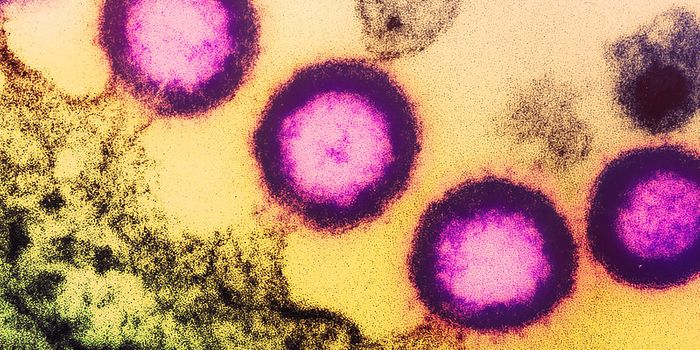

MAR 15, 2020MicrobiologyNew research has suggested that after long-term follow-up, HIV is no longer detectable in a patient that was previously ...

SEP 20, 2021Genetics & GenomicsHuman immunodeficiency virus (HIV) is a retrovirus, which is a type of virus that can write its genetic material into th ...